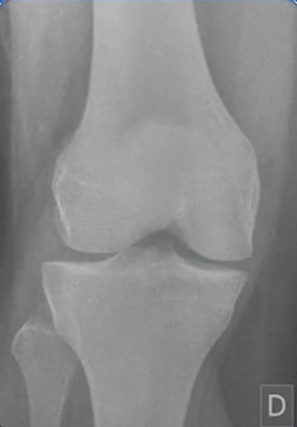

O contraste radiográfico pode ser definido como a diferença entre as densidades das estruturas registradas em um filme radiográfico, máximo (preto) e mínimo (branco) da imagem radiográfica, podendo ser influenciado pelo nível de exposição e pela radiação espalhada. Quanto maior a diferença das densidades maior é o contraste obtido em uma imagem radiográfica.

O fator de qualidade para controlar primariamente o contraste é o KV, também chamado de KVP ou DDP (diferença de potencial) que define um feixe de maior ou menor qualidade, quanto maior a qualidade mais energético é o feixe, e quanto menor a qualidade menos energético. Quando o KV tem uma alta qualidade obtém um grande poder de penetração sendo assim chamado de raios duros, o mesmo vale para quando se tem uma baixa qualidade sendo chamado de raios moles.

Alto contraste

- Pouco tons de cinza

- Visto com facilidade o que é negro e o que é branco

Baixo contraste

- Difícil visualização do que é negro e o que é branco

- Muitos tons de cinza

- Alta kilovoltagem = Baixo contraste visual e grande escala de contraste

- Baixa kilovoltagem = Alto contraste visual e curta escala de contraste